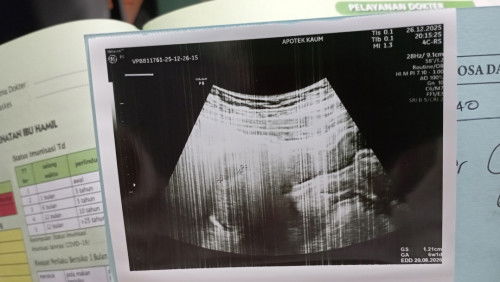

USG trimester 1

Ada yg sama gk bunda? Cek di bidan katanya udah 9 Minggu, tapi pas di USG ternyata baru 6minggu. Terus baru keliatan kantongnya aja. Gapapa kan ya? Sedih bgt😢